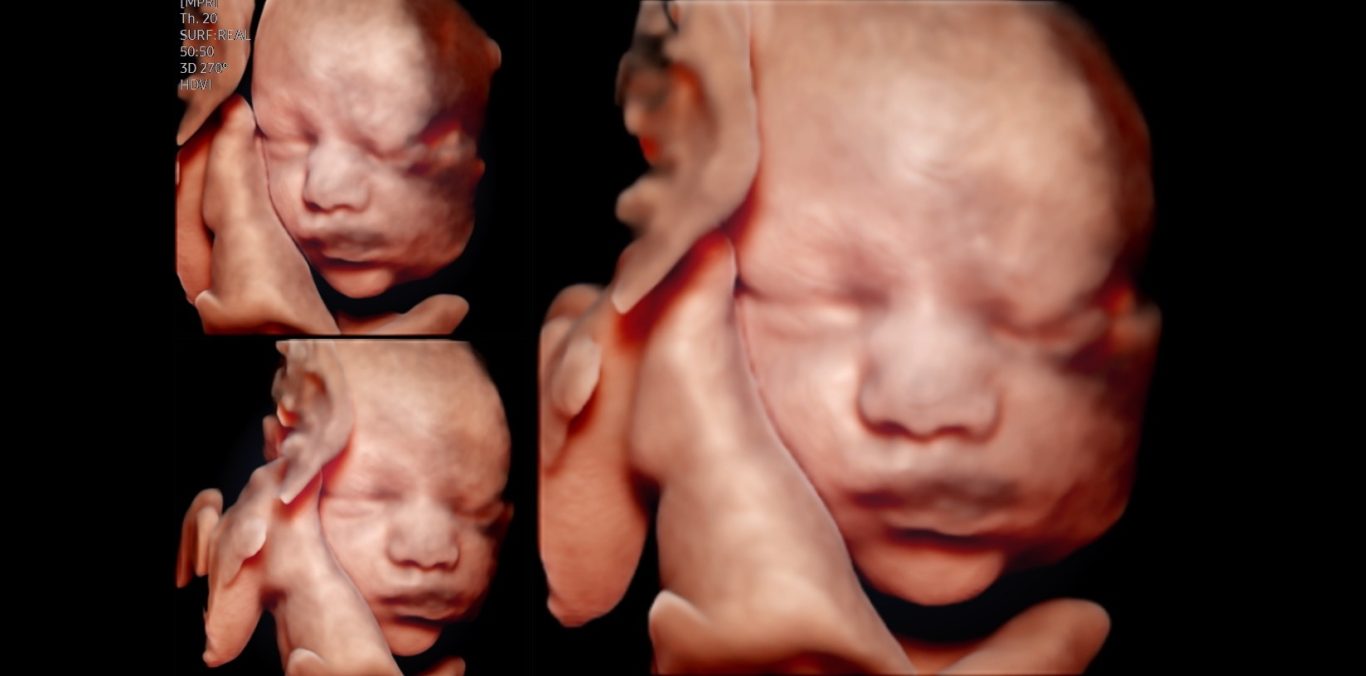

„Feindiagnostik“: 20-24 SSW

Wir schauen Ihr Kind im Ultraschall detailliert von Kopf bis Fuß an. Mit Fortschreiten der Schwangerschaft liegt der Fokus hier besonders auf der Entwicklung von Herz und Kopf Ihres Kindes. So können wir Besonderheiten frühzeitig erkennen, die Schwangerschaft optimal begleiten und die Geburt bestmöglich vorbereiten. In manchen Fällen ist eine Behandlung bereits während der Schwangerschaft möglich.

Je nach Fragestellung kann diese Untersuchung auch zu einem deutlich früheren oder späteren Zeitounkt sinnvoll sein.